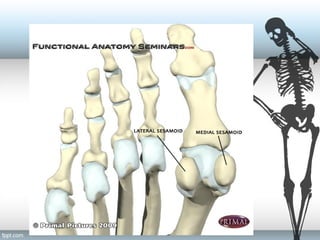

Plantar Plate

• 2 seasmoids

incorporated into

tendons of FHB

• Plantar Plate formed

by tendons of

Adductor Hallucis,

Abductor Hallucis,

FHL and Joint

Capsule

Collateral Ligaments

Sesamoid Ligaments

Hood Ligament